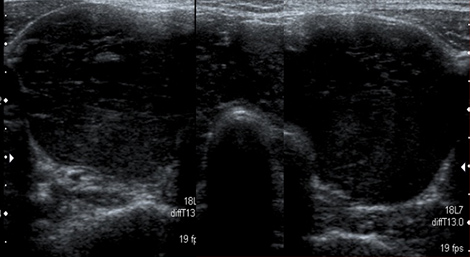

IgG4関連甲状腺炎の超音波(エコー)画像。甲状腺の両葉はびまん性に顕著に腫大し、内部は低~無エコー。

甲状腺は、頸部にある蝶のような臓器で、甲状腺ホルモンを分泌しています。IgG4関連甲状腺炎では、甲状腺の腫大に伴う頸部の腫脹、頸部痛、呼吸苦、嚥下障害や甲状腺ホルモン分泌低下に伴う耐寒性の低下、徐脈などの症状が出現します。

IgG4関連甲状腺炎の厳密な頻度は不明ですが、自己免疫性膵炎患者の約19%に甲状腺機能低下症を伴うことが報告されています。